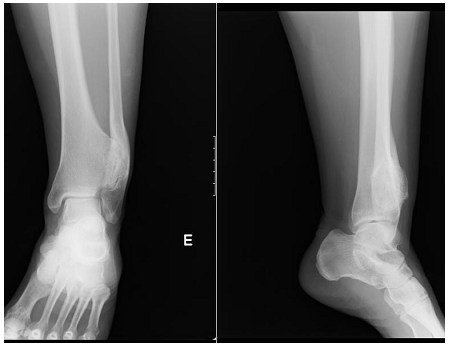

The authors present the case of a female patient, 45 years old, with neoformation in the left tibia, with several years of evolution. It was a massive osteochondroma of the distal tibia involving the left tibio-peroneal syndesmosis (Figure 1) and fibula deformity. The patient observed apparent increase in size in recent years with episodes of associated pain or discomfort in this location.

Figure 1 Left ankle X-Ray that demonstrates exostosis in the distal tibia, causing pressure and deformity in the fibula.

Physical examination revealed normal range of mobility and swelling of regular contours of the anterolateral region of the left ankle, hard, painless to palpation, without neurovascular compromise and without ankle instability. No other exostosis in the limbs was observed.